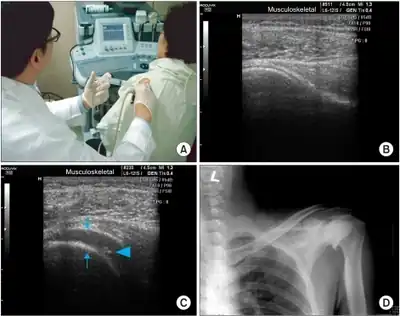

Imaging studies are not required for diagnosis but may be used to rule out other causes of pain. Radiographs are often normal but imaging features of adhesive capsulitis can be seen on ultrasound or non-contrast MRI. Ultrasound and MRI can help in diagnosis by assessing the coracohumeral ligament, with a width of greater than 3 mm being 60% sensitive and 95% specific for the diagnosis. Shoulders with adhesive capsulitis also characteristically fibrose and thicken at the axillary pouch and rotator interval, best seen as dark signal on T1 sequences with edema and inflammation on T2 sequences.[10] A finding on ultrasound associated with adhesive capsulitis is hypoechoic material surrounding the long head of the biceps tendon at the rotator interval, reflecting fibrosis. In the painful stage, such hypoechoic material may demonstrate increased vascularity with Doppler ultrasound.[11]